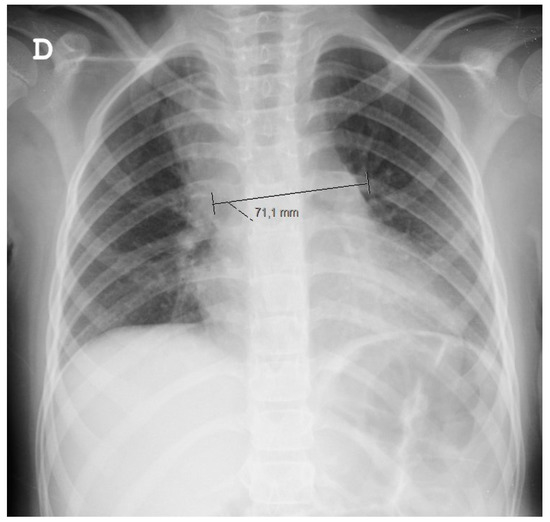

Since a chest X-ray (Figure 1) raised doubts about a superior right lobe condensation and a widened mediastinum, she was started on ampicillin and underwent a thoracic CT scan. The CT scan confirmed a widened mediastinum as a result of three fluid collections (the largest having 40 × 14 × 27 mm), topographically related to lymphadenopathies, which were associated with adjacent mediastinal tissue densification. Such findings prompted treatment conversion to large spectrum IV antibiotics (ceftriaxone and vancomycin).

Figure 1. Chest radiograph. D stands for “direita”—right in Portuguese.